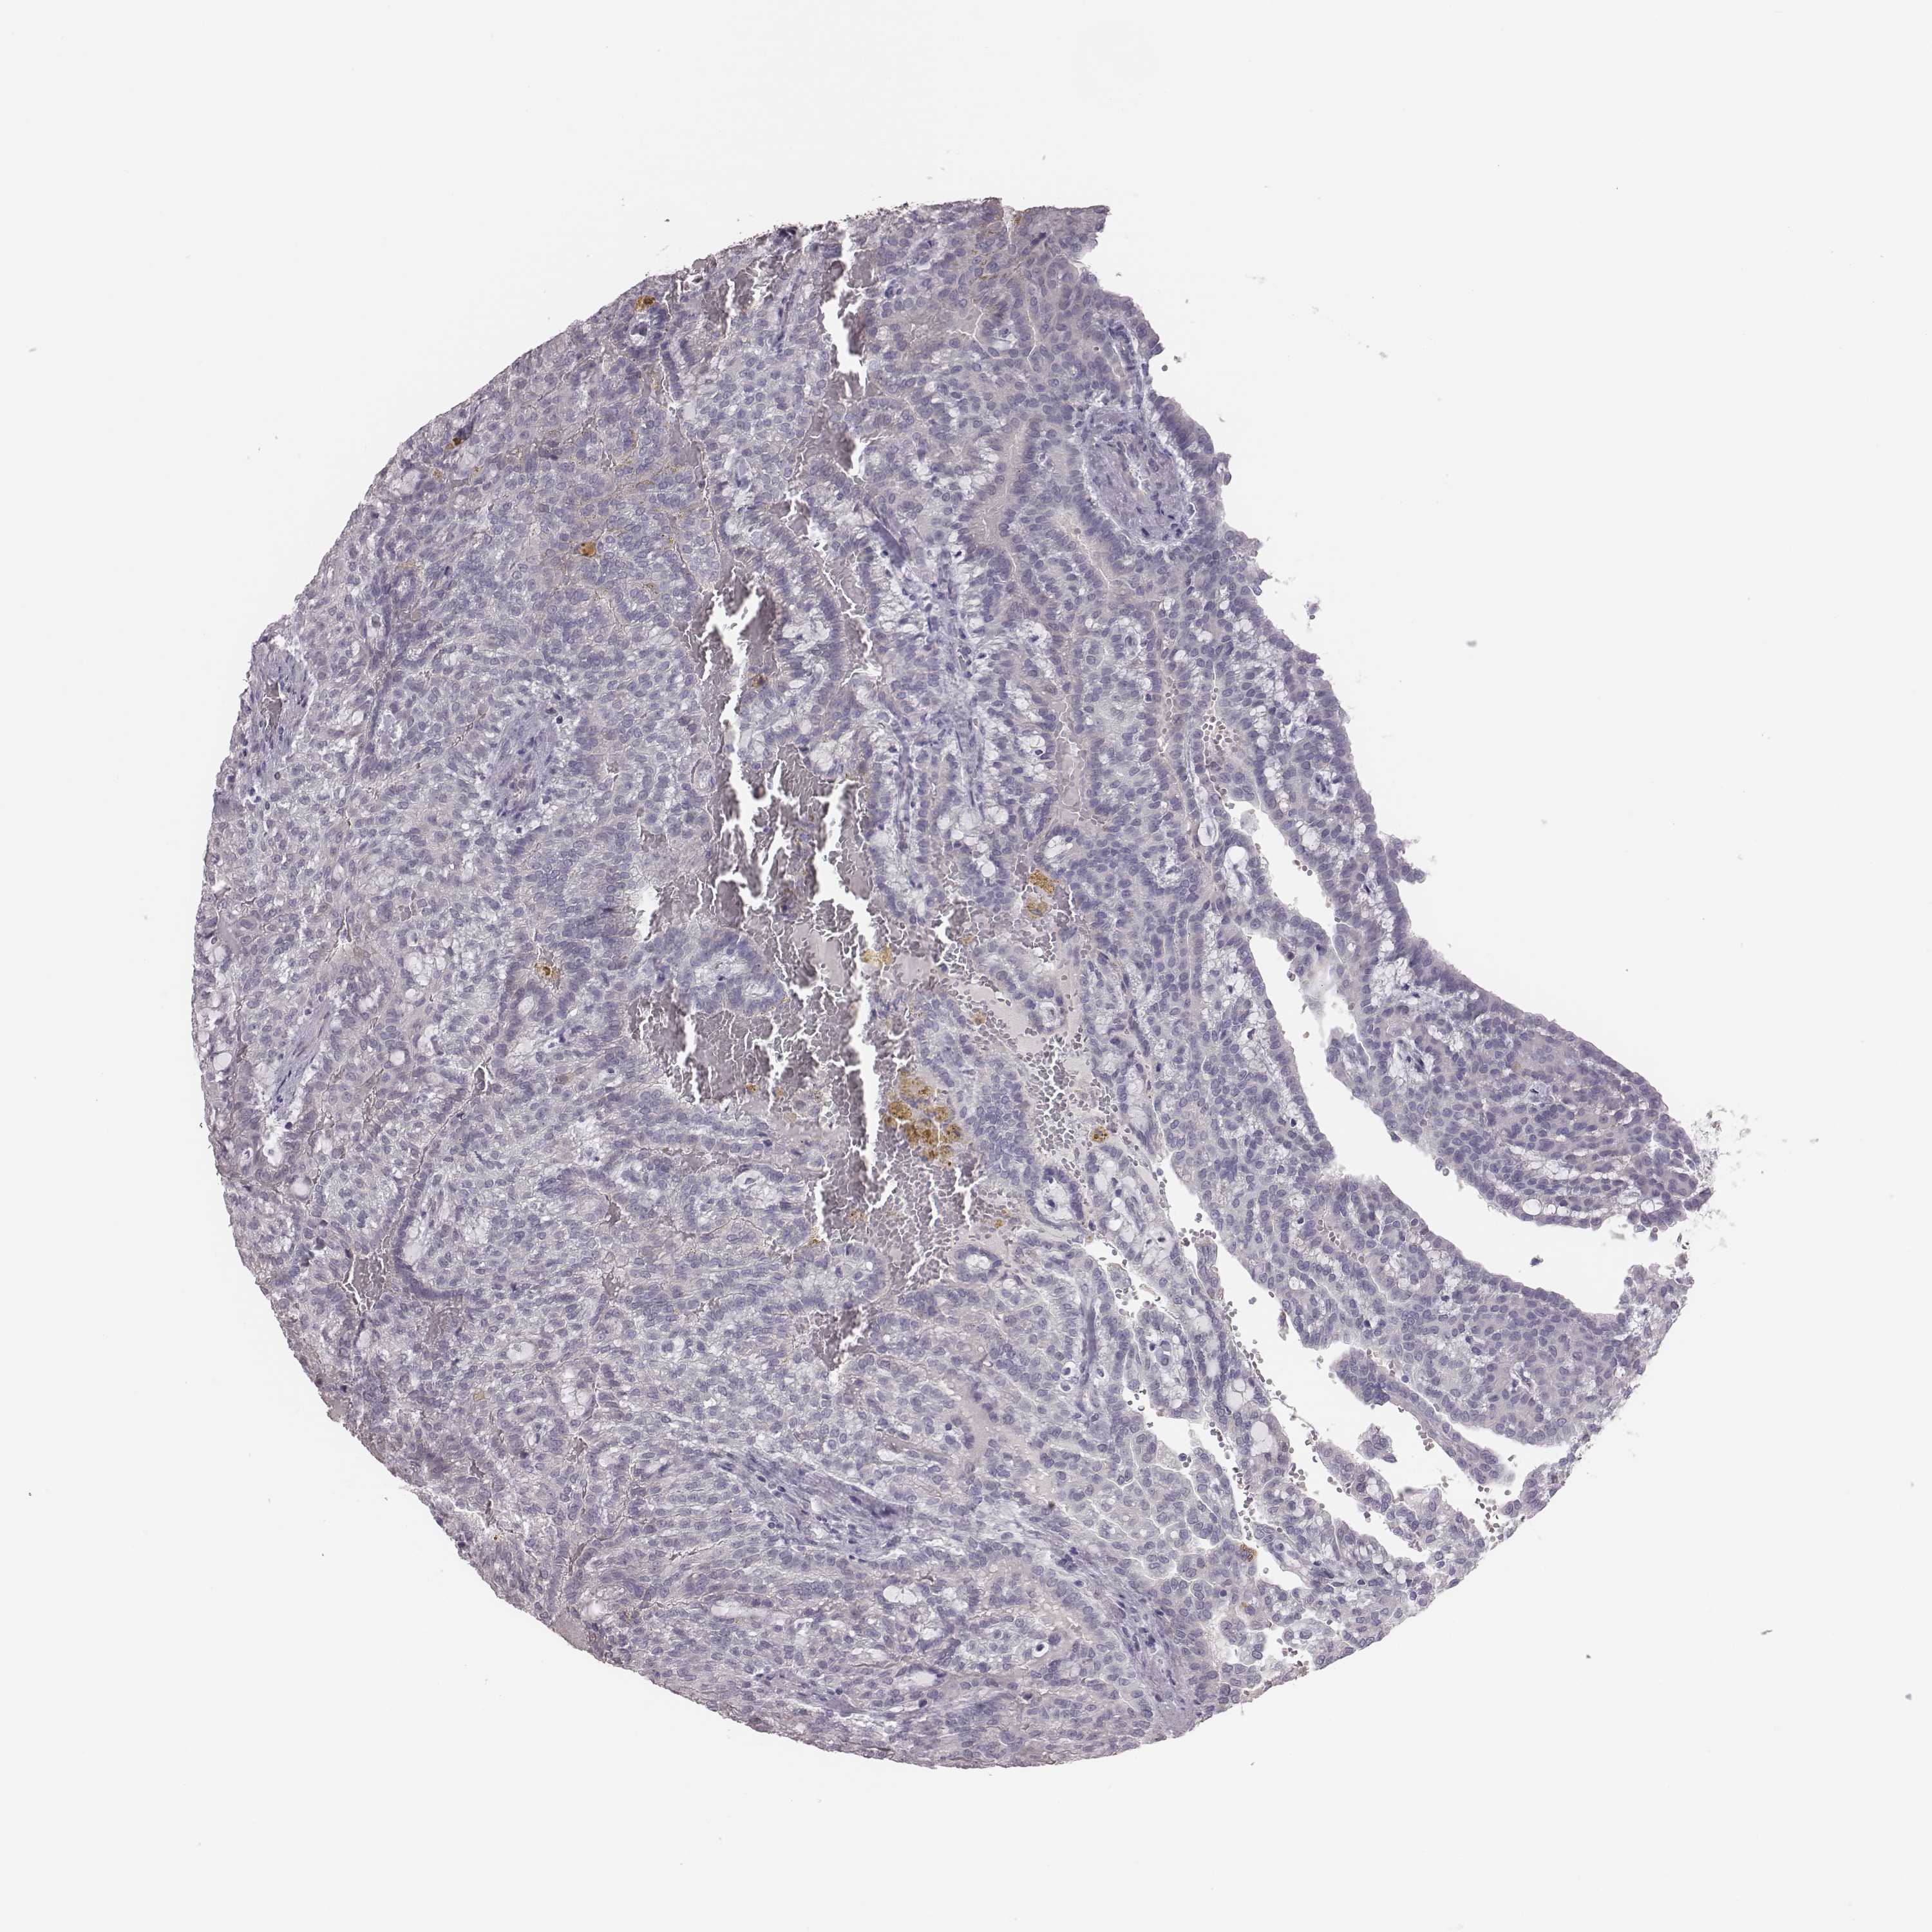

KIDNEY RENAL CLEAR CELL CARCINOMA (TCGA) - Interactive survival scatter ploti

The Survival Scatter plot shows the clinical status (i.e. dead or alive) for all individuals in the patient cohort, based on the same data that underlies the corresponding Kaplan-Meier plots. Patients that are alive at last time for follow-up are shown in blue and patients who have died during the study are shown in red.

The x-axis shows the expression levels (FPKM) of the investigated gene in the tumor tissue at the time of diagnosis. The y-axis shows the follow-up time after diagnosis (years). Both axes are complimented with kernel density curves demonstrating the data density over the axes. The top density plot shows the expression levels (FPKM) distribution among dead (red) and alive patients (blue). The right density plot shows the data density of the survived years of dead patients with high and low expression levels respectively, stratified using the cutoff indicated by the vertical dashed line through the Survival Scatter plot. This cutoff is automatically defined based on the FPKM cutoff that minimizes the p-score. The cutoff can be changed by dragging the vertical line or by entering a cutoff value in the square labeled "Current cut-off".

Under the Survival Scatter plot the p-score landscape (black curve; left axis) is shown together with dead median separation (red curve; right axis). Dead median separation is the difference in median mRNA expression between patients who have died with high and low expression, respectively. It is calculated as follows: median FPKM expression of dead patients with high expression - median FPKM expression of dead patients with low expression. This is intended to aid the user in visually exploring custom cutoffs and the associated p-scores and dead median separation.

Individual patient data is displayed and can be filtered by clicking on one or more of the category buttons on the top of the page. Categories describing expression level and patient information include: high, low, alive, dead, female, male and tumor stages. The scale of the x-axis can be toggled between linear and log-scale by clicking on the "x log" button. Mouse-over function shows TCGA ID, patient information and mRNA expression (FPKM) for each patient.

& Survival analysisi

Kaplan-Meier plots summarize results from analysis of correlation between mRNA expression level and patient survival. Patients were divided based on level of expression into one of the two groups "low" (under cut off) or "high" (over cut off). X-axis shows time for survival (years) and y-axis shows the probability of survival, where 1.0 corresponds to 100 percent.

PBK is not prognostic in Kidney Renal Clear Cell Carcinoma (TCGA)

Best expression cut offi

: 2.93

TCGA RNA samplesi

RNA-seq data is reported as average FPKM (number Fragments Per Kilobase of exon per Million reads), generated by the The Cancer Genome Atlas (TCGA) .

Normal distribution across the dataset is visualized with box plots, shown as median and 25th and 75th percentiles. Points are displayed as outliers if they are above or below 1.5 times the interquartile range. FPKM values of the individual samples are presented next to the box plot.

Average pTPM 2.3

Number of samples 521